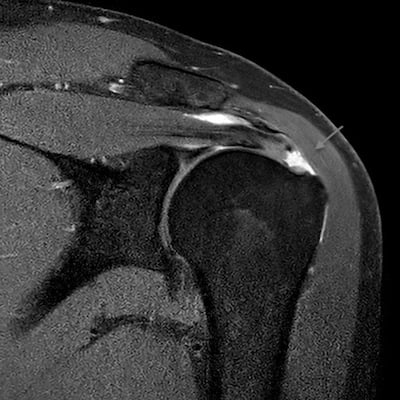

Η διάγνωση περιλαμβάνει κατά κύριο λόγο την λήψη ιστορικού και την κλινική εξέταση. Ο κ. Παναγόπουλος θα λάβει αναλυτικό ιστορικό και θα σας εξετάσει. Μία ακτινογραφία του ώμου θα βοηθήσει να αποκλειστούν άλλα αίτια πόνου, όπως οστεοαρθρίτιδα του ώμου ή ασβεστοποιός τενοντίτιδα. Ο κ. Παναγόπουλος θα σας υποβάλλει σε υπερηχογράφημα ώμου, για να επιβεβαιώσει την παρουσία ρήξεων στο στροφικό πέταλο. Ο υπέρηχος ελέγχει το πάχος του τένοντα, αλλά βοηθάει και στη δυναμική αξιολόγηση της πρόσκρουσης. Σε ορισμένες περιπτώσεις, ο ιατρός θα σας παραπέμψει για μαγνητική τομογραφία για την αξιολόγηση του μεγέθους της ρήξης ή τυχόν ατροφίας των μυών.